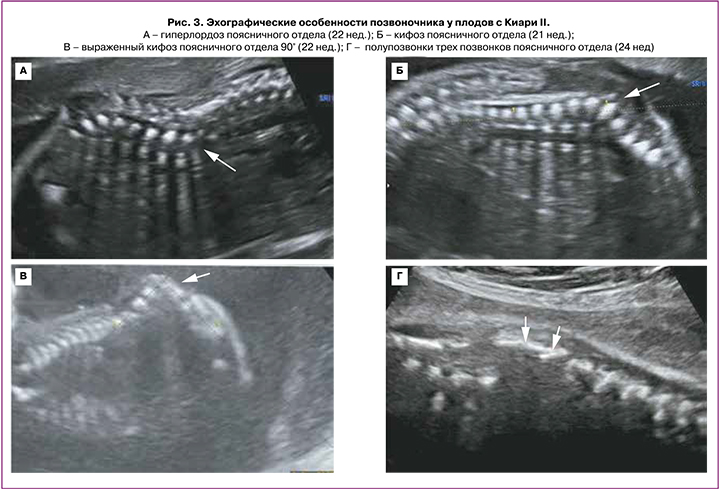

В сроке 12–14 недель у всех 5 плодов были выявлены следующие церебральные особенности: аномальное количество ликвора в боковых желудочках (в 2 случаях – «сухой мозг», в 3 случаях – сосудистое сплетение занимало менее 50% просвета бокового желудочка); сужение/отсутствие визуализации водопровода мозга со смещением его заднего контура к затылочной кости; форма мозжечка – «банан» (рис. 2). Начальный уровень расположения Spina Bifida по отношению к позвоночнику визуализировался с позвонков L2–L3; при этом у 1/5 плодов было выявлено выраженное искривление позвоночника (угол 90°) (рис. 3).

Во II триместре беременности во всех 20 случаях были выявлены общепринятые эхографические признаки Киари II: вклинение мозжечка в Большое затылочное отверстие с признаком его деформации (форма «банан»), изменение конфигурации костей черепа (форма «лимон»), вентрикуломегалия, наличие спинномозговой грыжи позвоночника. ММЦ и РШ определялись у 15/20 и 5/20 плодов соответственно. Начальный уровень расположения Spina Bifida по отношению к позвоночнику определялся у 2 плодов с позвонка T10, у 14 плодов – с L2–L3, у 4 – с L4–L5 (рис. 3). Средний срок беременности, когда проводилась детальная морфометрия церебральных структур, составил 23,9 (23,0–25,3) недель. Для 20 плодов были характерны изменения: вентрикуломегалия (10–17 мм независимо от уровня поражения спинного мозга), «клювовидный» тектум (крыша мозга), «заостренные» затылочные рога боковых желудочков, задержка формирования борозд (рис. 4, таблица). Средние значения ширины задних рогов боковых желудочков составляли: слева – 11,5 (9–16) мм, справа – 11 (5–17) мм. Дисгенезия мозолистого тела была выявлена у 3/20 пациентов. Для остальных 17 случаев было характерно незначительное укорочение длины мозолистого тела. Средние значения длины мозолистого тела составили 23,8 (14–29) мм (таблица). У половины плодов (55%) определялось дорсальное кистообразное расширение III желудочка. У 3 плодов из 20 с уровнем Spina Bifida L2–L3 была диагностирована межполушарная голопрозэнцефалия. При оценке тектума мы не выявили достоверно значимых различий в его длине по сравнению с нормативными значениями, однако у всех плодов была изменена его форма и расположение. Средние значения длины тектума составили 11,1 (9,5–14) мм. Лишь у 5/20 (25%) плодов длина тектума была более 11 мм, что соответствует более 2 стандартных отклонений для срока беременности 24–25 недель согласно исследованию Leibovitz Z. et al. [12]. У 80% (16/20) пациентов отмечалось нарушение формирования борозд островковых долей при типичном формировании остальных борозд полушарий мозга.